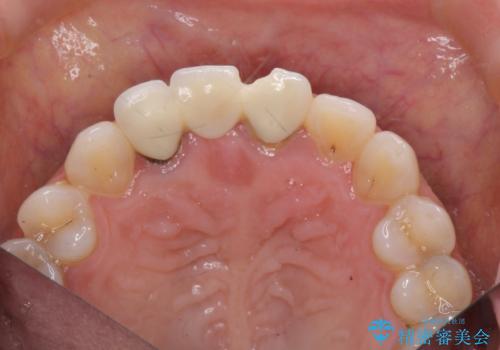

現在装着されているブリッジを除去したところ、歯ぐきよりも上に存在する歯質(縁上歯質)が少なく、土台の形態の悪さや不適合などさまざまな問題があります。

根管治療を行ったのち、歯周外科を行うことで、欠損部の歯ぐきの厚みを出し、縁上歯質を獲得することで、長期的な予後の見込めるブリッジを製作できる環境を整備していきます。

- 50.6万円(ジルコニアクラウン×3・仮歯×3・歯周外科)費用は治療当時の料金となります